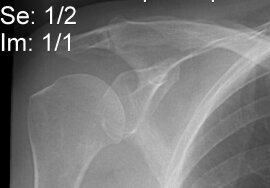

EM Orthopedics for the Medical Student: The Shoulder

Y Leibman, MD